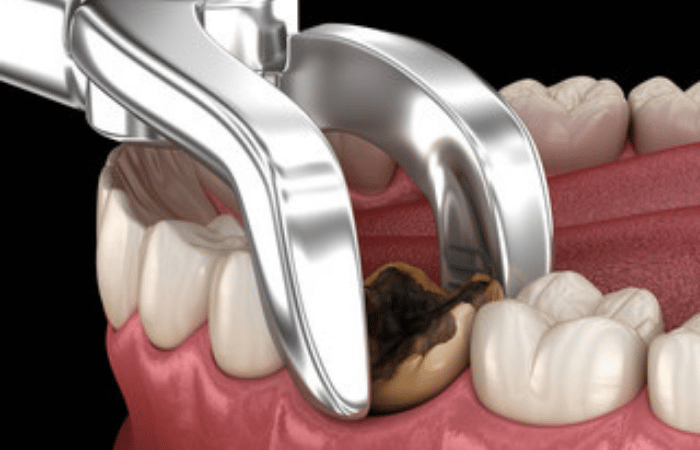

The Tooth Extraction Procedure:

- Extraction: Using specialized dental instruments, the dentist or oral surgeon will gently loosen the tooth from its socket in the jawbone. For multi-rooted teeth, the tooth may be divided into sections to facilitate extraction.

- Removal: The tooth is carefully lifted and removed from the socket. In some cases, a small amount of bone may need to be removed.